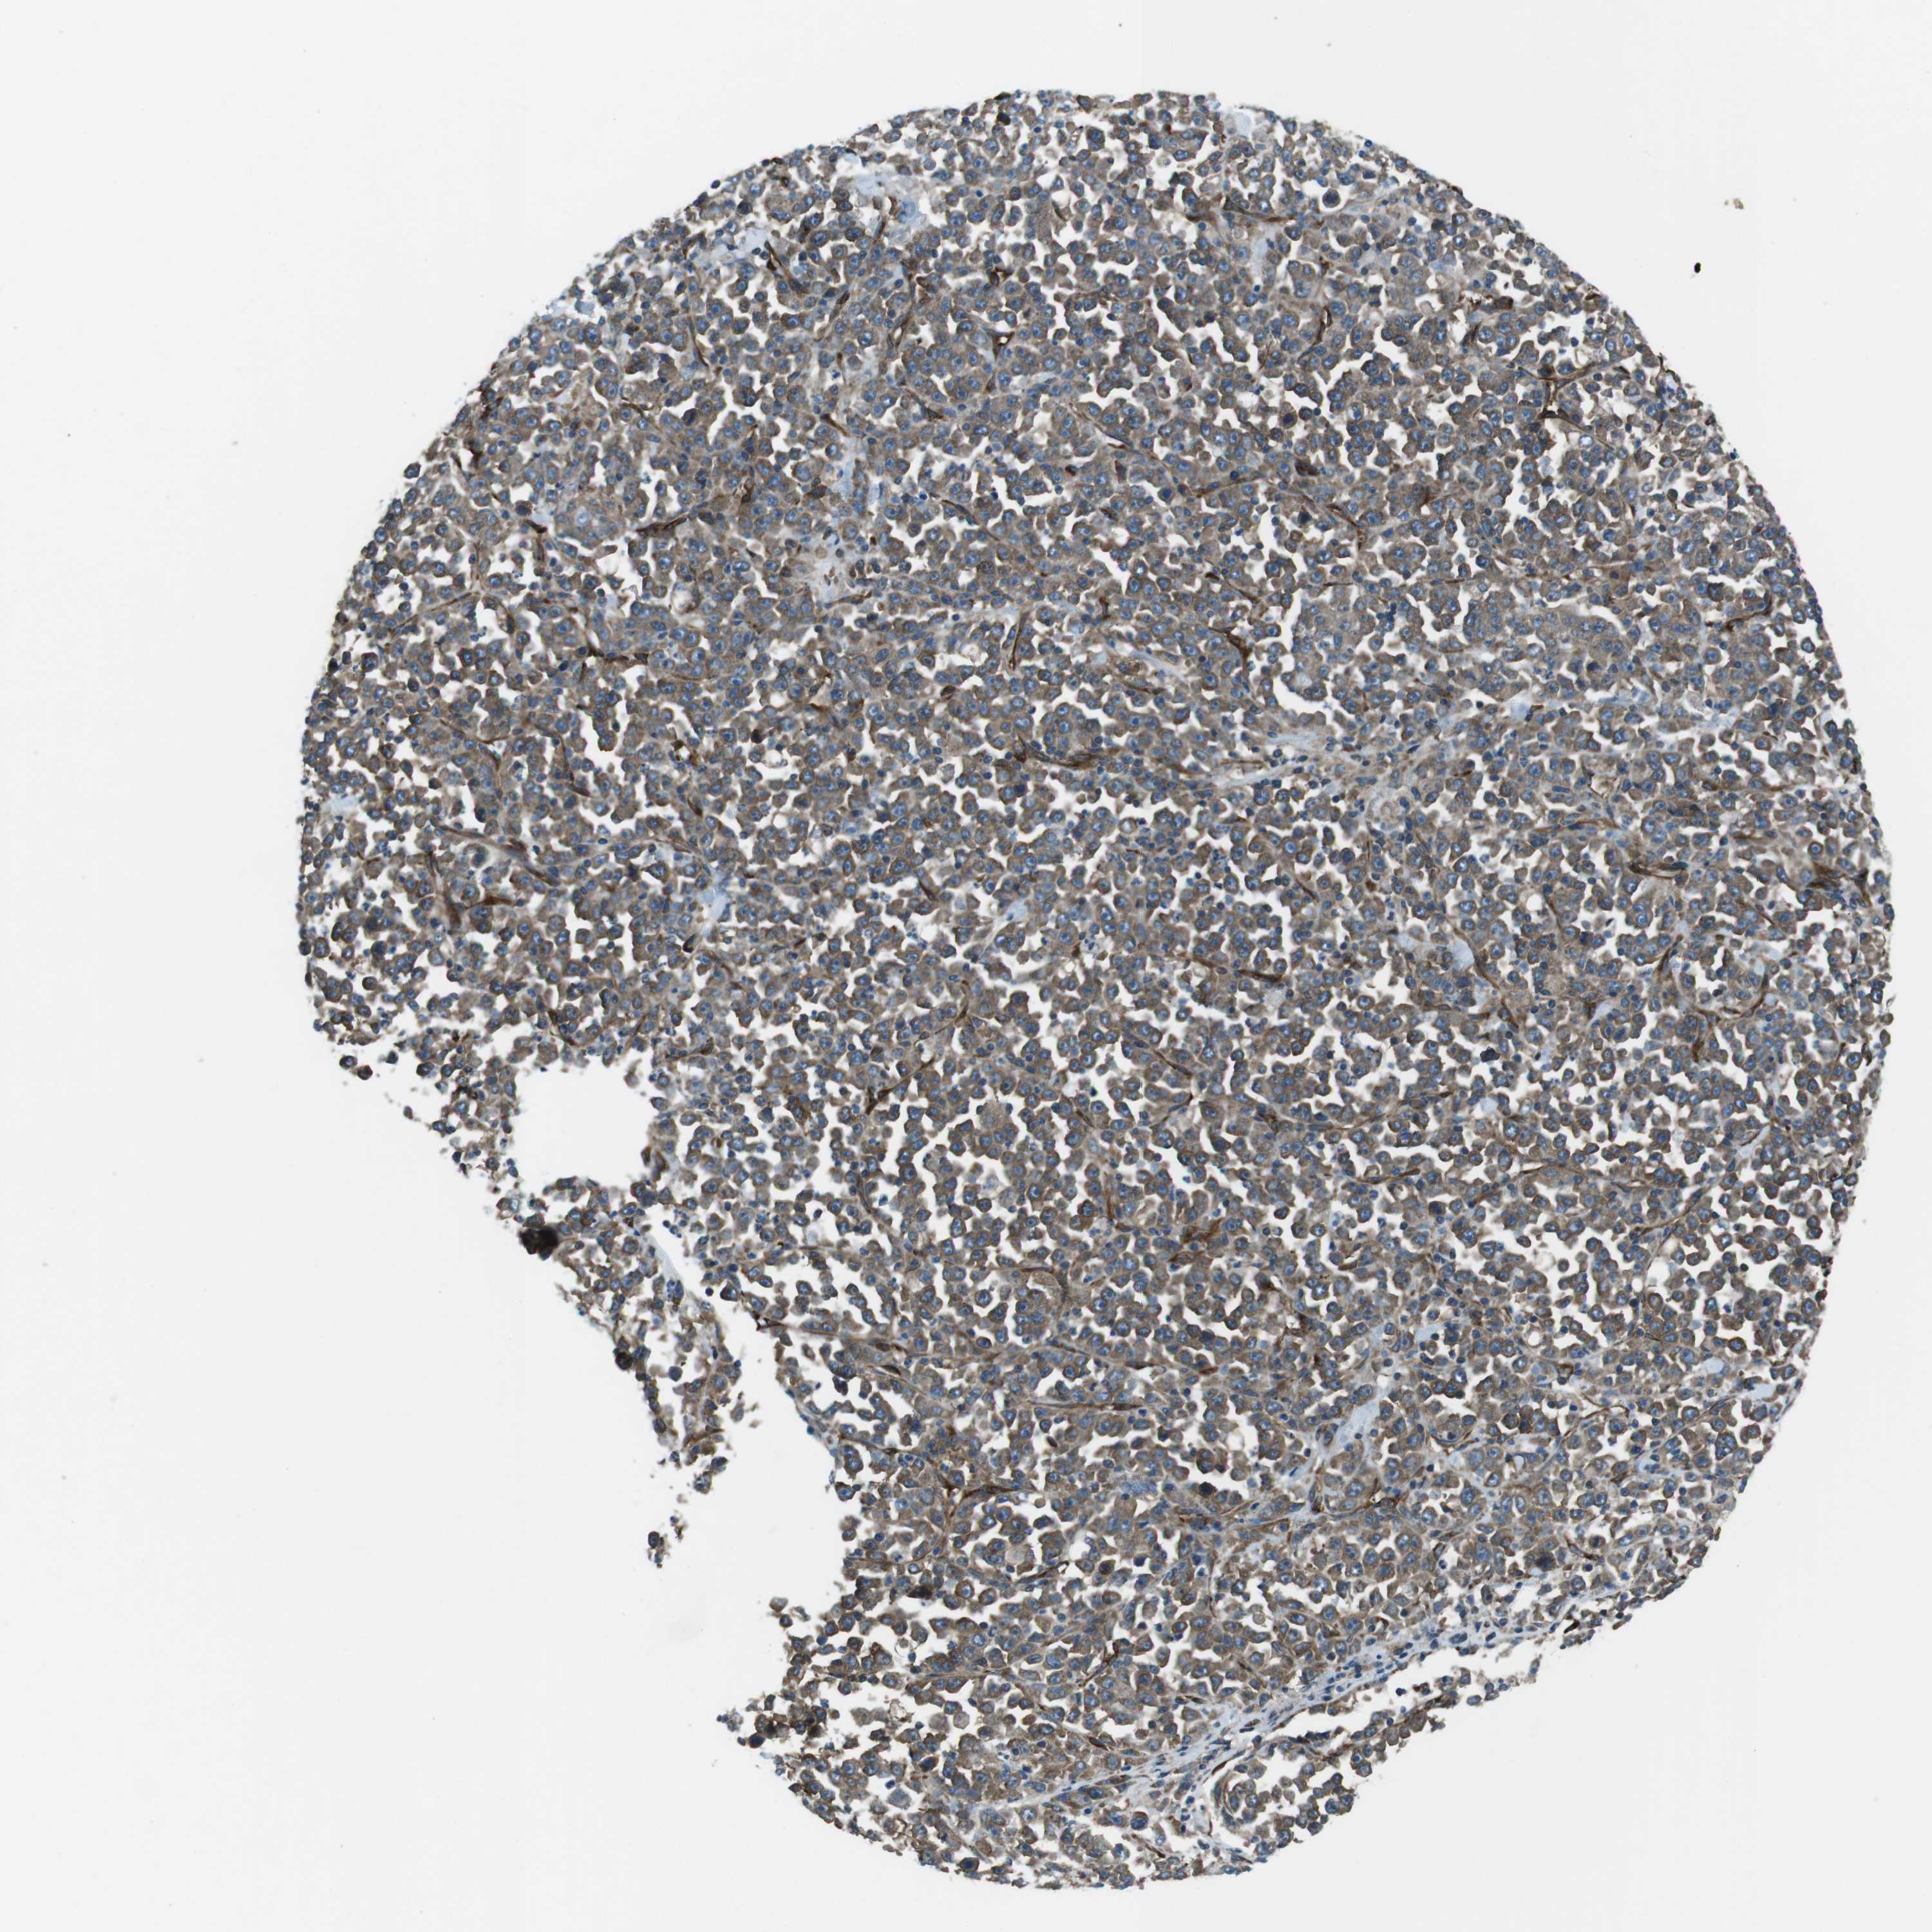

STOMACH CANCER - Protein expressioni

A mouse-over function shows sample information and annotation data. Click on an image to view it in a full screen mode. Samples can be filtered based on level of antibody staining by selecting one or several of the following categories: high, medium, low and not detected. The assay and annotation is described here.

Antibody staining in the annotated cell types in the current human tissue is reported as not detected, low, medium, or high, based on conventional immunohistochemistry profiling in selected tissues. This score is based on the combination of the staining intensity and fraction of stained cells.

Each image is clickable and will lead to virtual microscopy that enables deeper exploration of all samples and also displays staining intensity scores, fraction scores and subcellular localization as well as patient and tissue information for each sample.

Antibody HPA003178

Antibody HPA017876

Antibody CAB015331

Staining

High

Medium

Low

Not detected

Intensity

Strong

Moderate

Weak

Negative

Quantity

>75%

75%-25%

<25%

None

Location

Nuclear

Cytoplasmic/membranous

Cytoplasmic/membranous,nuclear

Adenocarcinoma, NOS

Adenocarcinoma, High grade